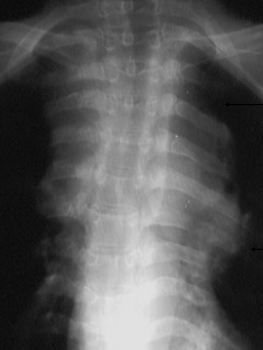

DESCRIERE:

DX: hiperplazie timică bilaterală

DD: